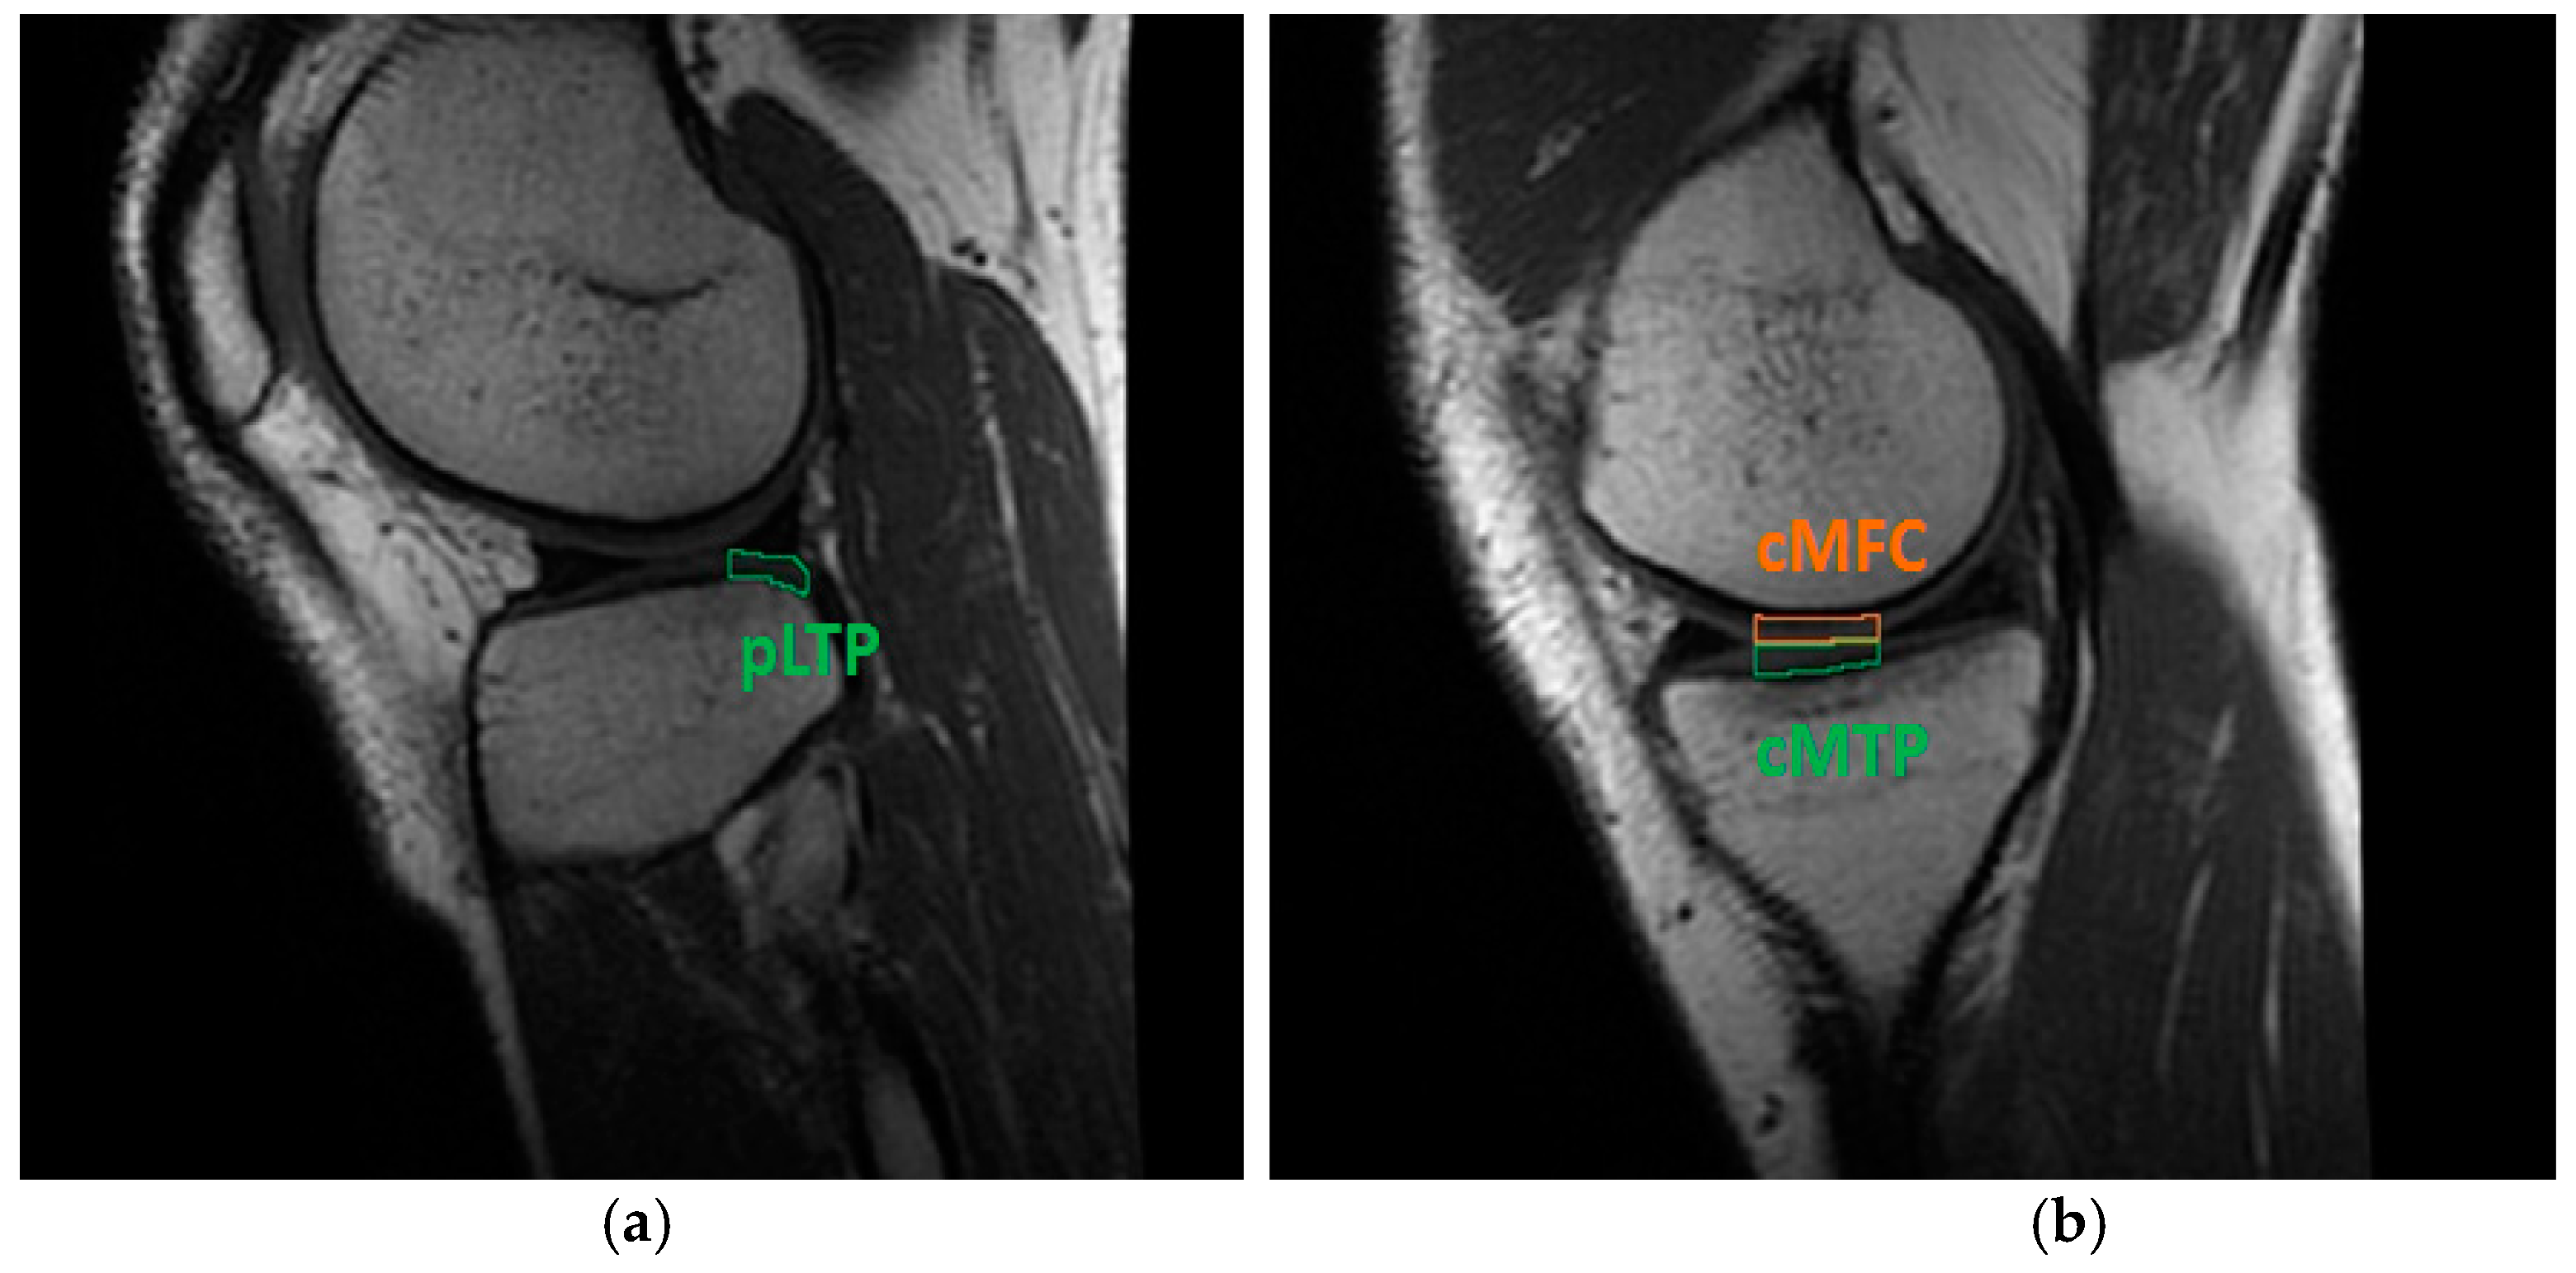

| T2 (ms) | pLTP | cMTP | cMFC | |

| Pre-op | 42.2 ± 3.9 | 37.1 ± 3.4 | 35.7 ± 5.2 | |

| FU4 | 42.2 ± 4.2 | 36.8 ± 3.4 | 33.7 ± 4.0 | |

| FU18 | 42.7 ± 3.7 | 35.4 ± 3.1 | 35.0 ± 4.3 | |

| Control | 38.3 ± 3.4 | 38.0 ± 5.4 | 33.9 ± 4.5 |